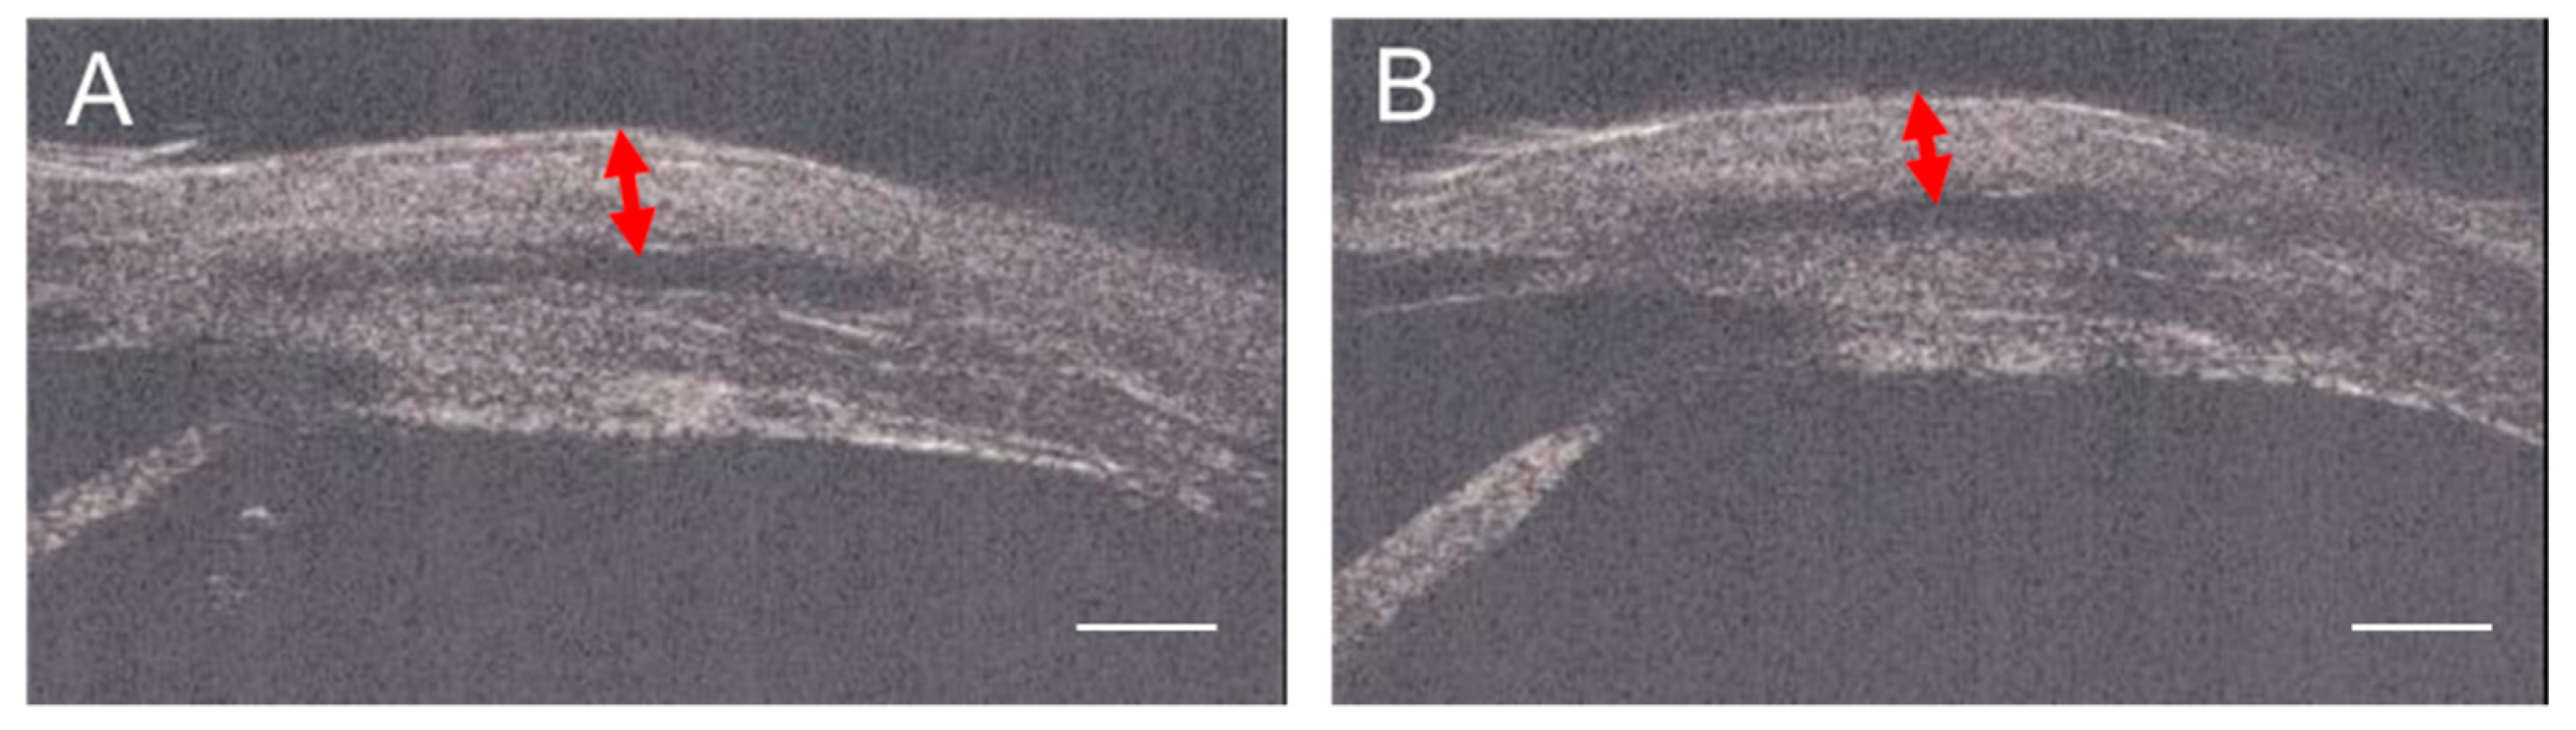

2.2.3. Ultrasonic Biomicroscope (UBM) Assessments